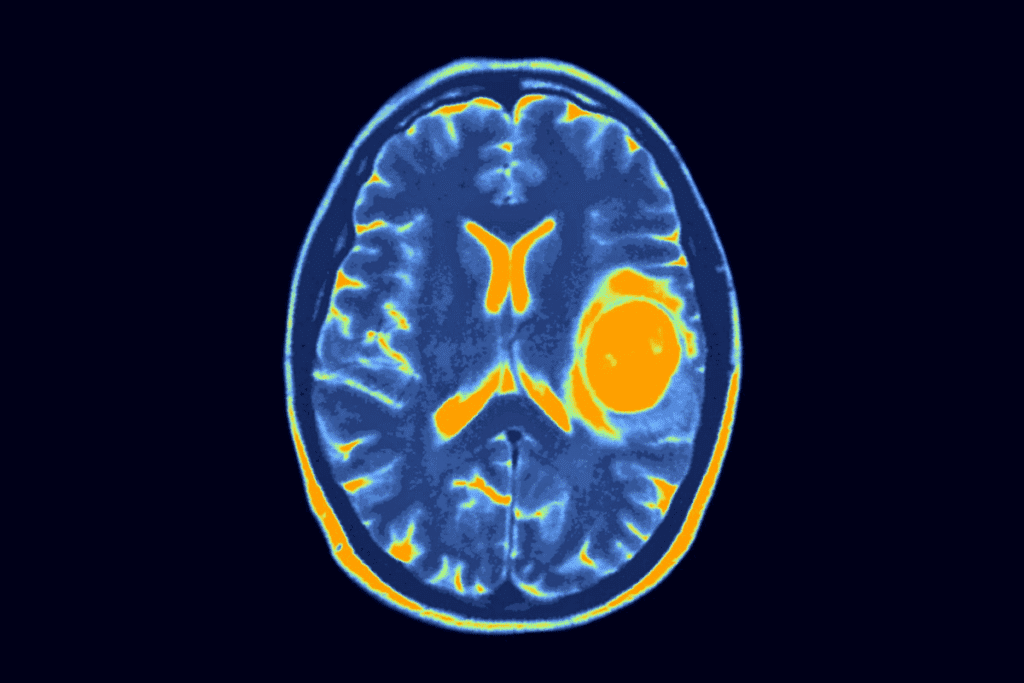

Diagnostic Challenges in Asymptomatic Cases

Asymptomatic brain tumors in children are hard to diagnose. They don’t show symptoms, making it tough for doctors to find them. This is because there are no clear signs to look for.

Current Limitations in Screening and Detection

Screening for brain tumors has its limits, mainly in cases without symptoms. MRI and CT scans are very good at finding tumors. But, they’re not used for regular checks because of the cost, availability, and worries about radiation.

We usually wait for symptoms to appear before testing further. But, for silent brain tumors, this can cause a delay in finding out what’s wrong.

Diagnostic Procedures for Detecting Silent Brain Tumors

Finding brain tumors in kids without symptoms is tough. New medical tech has helped us spot these tumors early. This is even when they don’t show any symptoms.

Imaging Technologies and Their Effectiveness

Imaging tech is key in finding silent brain tumors. Magnetic Resonance Imaging (MRI) stands out. It gives clear brain images, helping doctors find tumors early.

It’s a vital tool in finding tumors without symptoms.

Computed Tomography (CT) scans also help find brain tumors. They’re fast and easy to get, but they use radiation. They might not show soft tissue details as well as MRI.